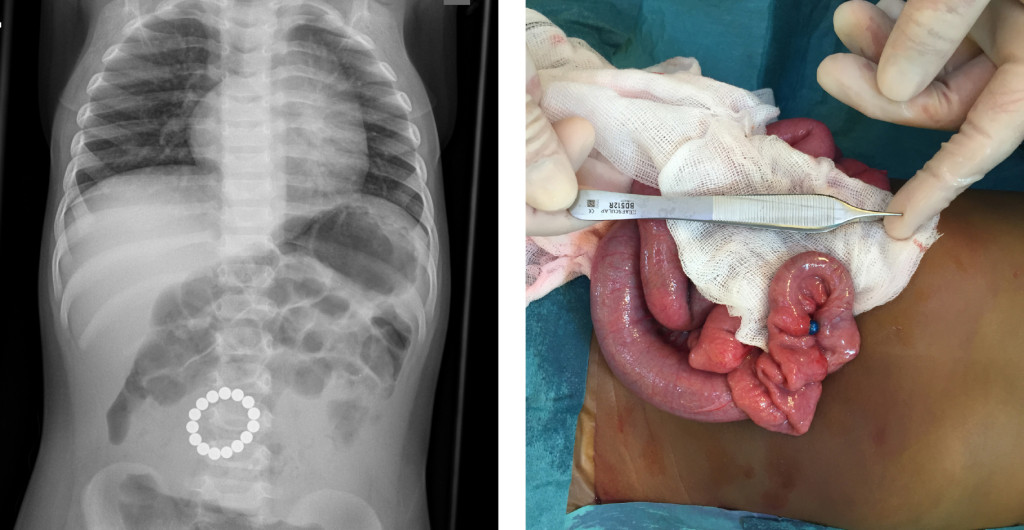

The X-ray shows a ring of circular foreign bodies inside the abdomen of a one-year-old child. The patient had been admitted with a two-day history of vomiting.

The patient underwent laparotomy. A ring of magnetic beads was found in the small intestine about 70 cm from the ligament of Treitz. One of the beads had eroded through the intestinal wall, as can be seen in the perioperative photograph. The magnetic beads were removed, and intestinal resection with primary anastomosis was performed. The patient was discharged on the fifth postoperative day in good general condition, but was readmitted two days later following wound dehiscence. This was surgically corrected, and the child was discharged on the third day after the procedure.